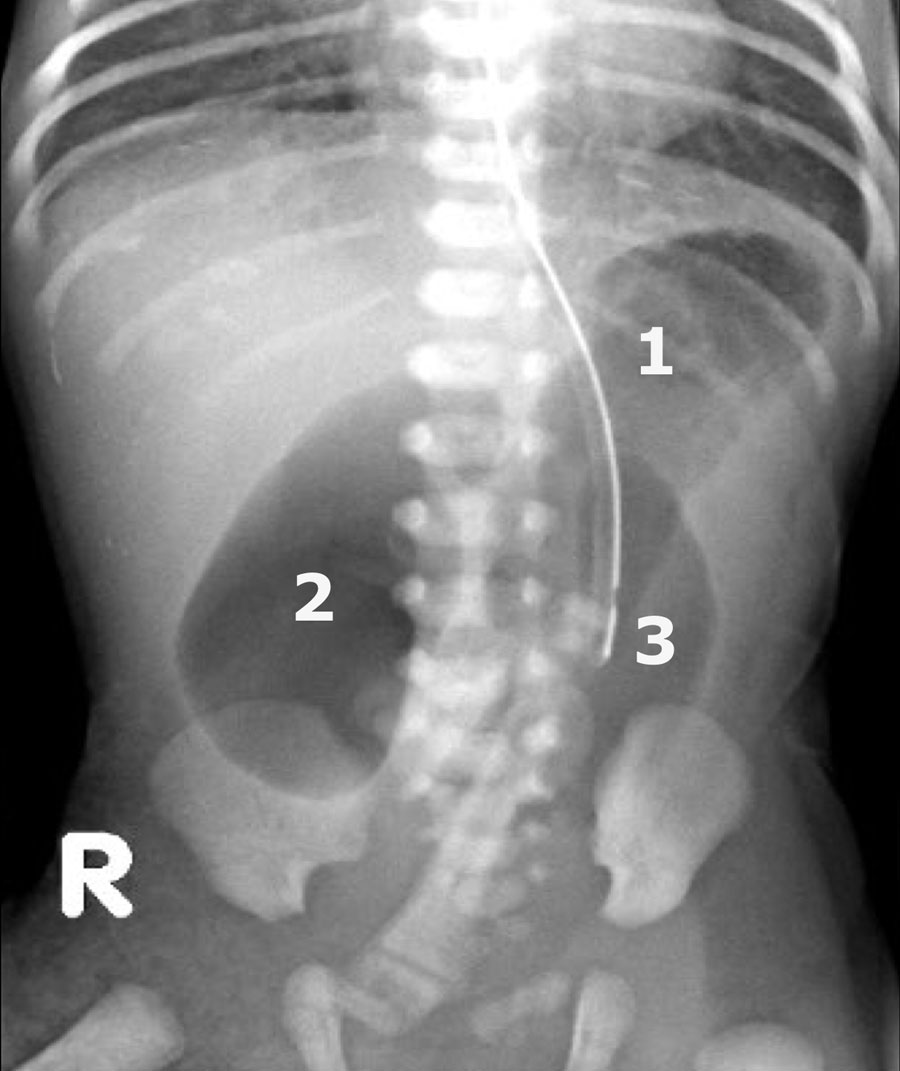

Đây là một trường hợp điển hình khác của viêm ruột hoại tử.

Lưu ý hình ảnh khí trong tĩnh mạch cửa (mũi tên) và các nhánh tĩnh mạch cửa ngoại vi.

Dấu hiệu này được thấy trên X-quang và siêu âm.

Ở bệnh nhân viêm ruột hoại tử này, hãy chú ý các bóng khí trong thành ruột và trong nhu mô gan.